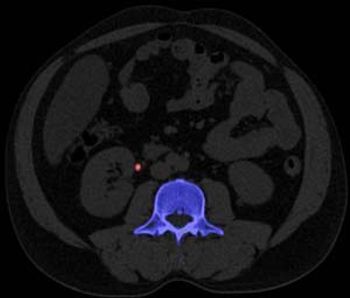

Yes, size does matter, but it is certainly not the only way to monitor the efficacy of cancer treatment. The way in which lesions are measured is extremely important as well, ECR delegates were told at a special focus session on the assessment of tumor response.